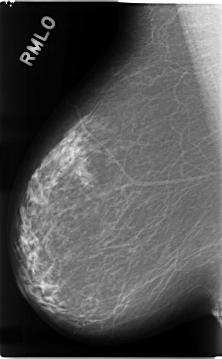

C_0112_1.RIGHT_MLO

RIGHT_CC LINES 4672 PIXELS_PER_LINE 2736 BITS_PER_PIXEL 12 RESOLUTION 50 NON_OVERLAY

RIGHT_MLO LINES 4664 PIXELS_PER_LINE 2880 BITS_PER_PIXEL 12 RESOLUTION 50 NON_OVERLAY